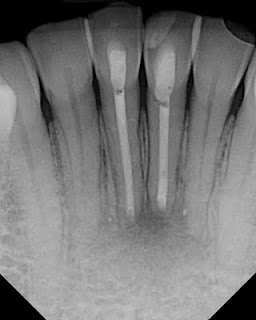

This patient was kicked in the face by a horse in 1998. Teeth were displaced (luxated). She repositioned them herself. RCT’s on #24 and #25 were done in 2008 by her general dentist. In

Jan 2011 she is having pain, percussion sensitivity, normal probings, adjacent teeth WNL. These teeth are diagnosed as: Prior RCT’s w/ Symptomatic Apical Periodontitis.

Axial and sagittal views in CBCT verify that these are single canals incisors. It also shows us the extent of the bone loss prior to our surgical access.

Due to the large size of the canals and over extension of the previous RCT, it was recommended to treat these teeth surgically with an apicoectomy.

Apicoectomy completed with MTA retrofill.